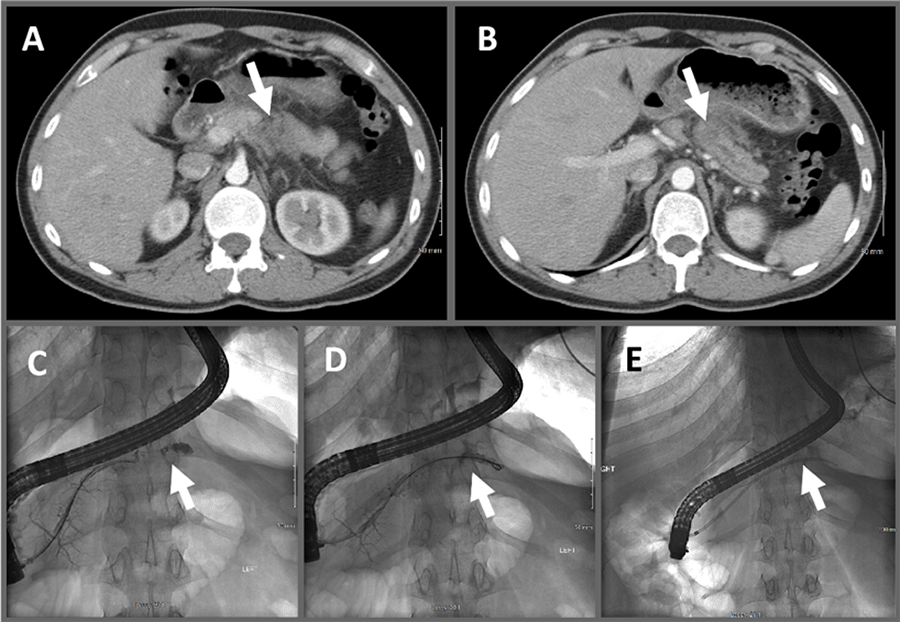

The patient is a 30-year-old male 1.5-pack-per-day smoker who suffered mild epigastric trauma while wrestling with co-workers, after which he developed progressive abdominal pain and clinical pancreatitis. A CT scan of the abdomen showed inflammation surrounding the body of the pancreas and a 1.6 cm low attenuation area with associated upstream pancreatic duct (PD) dilation (Figure 1A and Figure 1B). Given the history of trauma in a young patient, this abnormality was suspected to represent a site of PD disruption. The patient underwent ERCP showing PD disruption with contrast extravasation at this site, which was crossed with a wire and stented (Figures 1C‒1E) with a resolution of his pain.

Figure 1. Imaging Findings Demonstrating Peripancreatic Inflammation and PD Disruption. Published With Permission

Contrast-enhanced axial CT images showing A) inflammatory changes at pancreatic body; and B) 1.6 cm area of hypoattenuation with associated upstream PD dilation. ERCP fluoroscopy images show extravasation at C) disrupted PD, which was D) crossed with wire and E) stented. Arrows indicate key findings for each image.